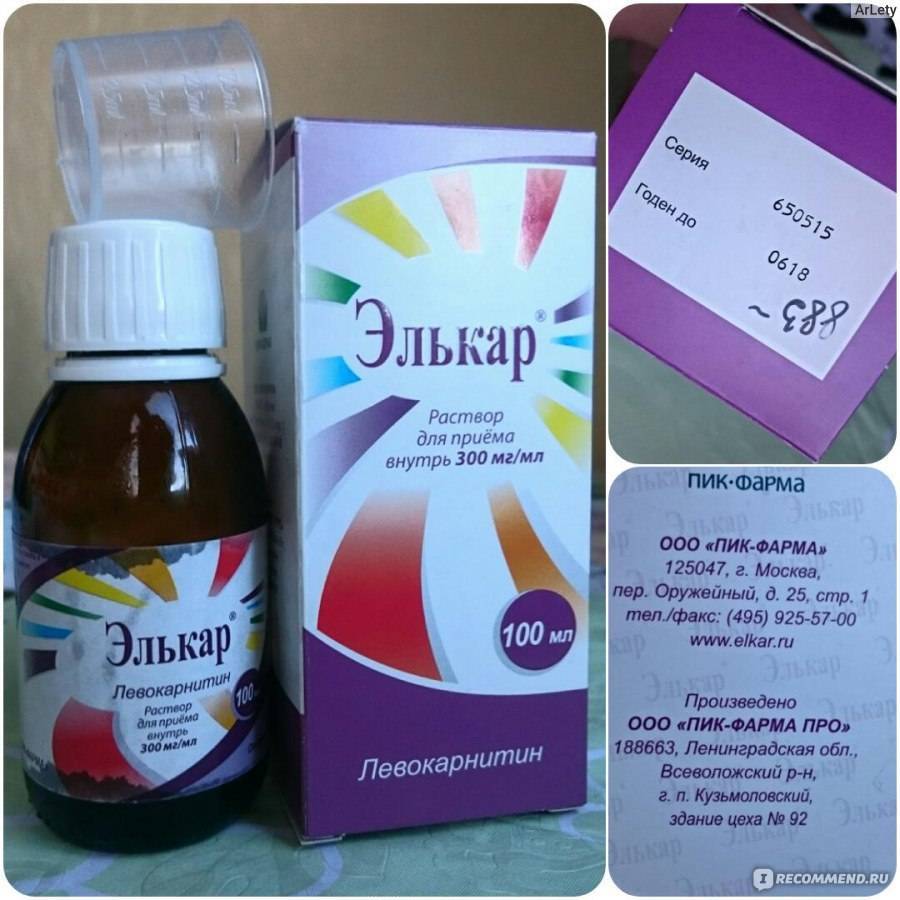

Элькар – это универсальное лекарственное средство, которое входит в комплексные схемы лечения различных нарушений здоровья у взрослых и детей. Он применяется в удобных лекарственных формах (раствор для приема внутрь, сироп и капли для детей, раствор для инъекций). В зависимости от патологии и возраста больного лечащим врачом подбираются индивидуальные схемы лечения с уточнением:

30% капли для приема внутрь с удобным дозатором для детей или мерной ложкой или стаканчиком для старших пациентов.

Приобретая Элькар в каплях, обратите внимание на инструкцию по приему, особенно, когда это касается детей. Элькар в каплях выпускается в виде 20% раствора и Элькар 30%

Средство традиционно выпускается во флаконах темного стекла объемом от 25 до 100 мл, к которым может прикладываться мерная ложка или мерный стаканчик. С учетом особенностей дозировки, даже самого маленького флакона хватит на полноценный курс для взрослого человека, впрочем, зависит это и от способа применения.